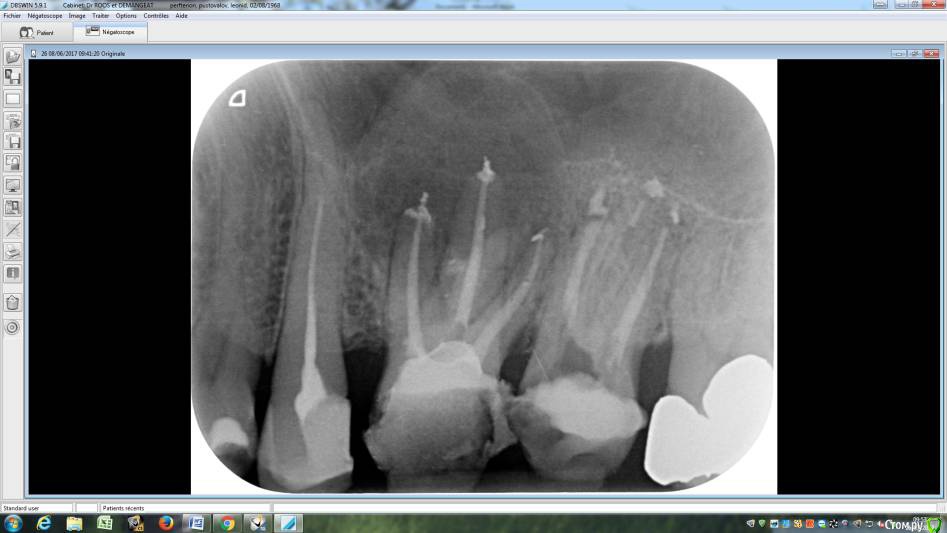

LeoRuss Опубликовано 20 февраля, 2018 Поделиться Опубликовано 20 февраля, 2018 (изменено) Здравствуйте уважаемые метры, в очередной раз обращаюсь к вам за советом.Чуть меньше года назад эндодонтическим методом в полном соответствии с вашими рекомендациями была пролечена киста 26.( http://forum.stom.ru/topic/34508-podsadka-kosti-pri-kiste-nuzhna-li-v-dannom-slucha/ ) При вскрытии зуба выявилась неприятная картина: оба титановых штифта в далеком ‘94м были завернуты мимо корневых каналов прямо в челюсть ;(Док все демонтировал, прочистил под микроскопом и каналы и дыры от штифтов и замуровал МТА : спустя 8 месяцев - 10/2017 : И вроде бы все чудесно, но пару раз за это время десна вокруг зуба воспалялась, и зуб становился более подвижным, но все проходило после 2-3-5 дневного интенсивного полоскания хлоргексидином. Три недели назад была наконец то установлена коронка на соседний 27й, десна с внутренней стороны 26ки тогда была тоже припухшей и протезист посоветовал сходить на контроль к эндодонтисту. Напросился и сходил через неделю, десна за это время еще чуть распухла (только со стороны языка), стало больно при легком нажатии на десну в районе верхушки корня ближнего к 25ке и при покачивании зуба. Док сделал снимок, сказал что все чисто и он понятия не имеет почему все надулось. Вариант удаления забраковал, сказал что по его мнению все хорошо, и можно уже ставить коронку. А вот в импланте смысла никакого, тем более что кости для него пока недостаточно, тк межкорневая область еще не дозаросла. Посоветовал терпеть и.. поставить коронку, тк нагрузка на зуб при жевании должна активировать заживление.Но жевать на этой стороне я стал почти месяц назад, сразу после установки временной коронки на 27, вот с тех пор с 26кой все хуже и хуже. За последние полнедели опухоль сильно увеличилась, и между 25/26, и в сторону нёба, дергает в ритме пульса. Появились отголоски боли в носоглотке и в заглазье.Терпеть уже плохо получается, да и смысла не вижу. Вижу два варианта:1. Удалять 26 чтоб не мучаться, с последующей имплантацией, но как быть с нехваткой кости?2. Вскрыть каналы и прочистить еще раз, но даст ли это хоть что то, да и возможно ли в принципе? В любом случае хотел бы узнать ваше мнение, спасибо ! Изменено 20 февраля, 2018 пользователем LeoRuss Ссылка на комментарий